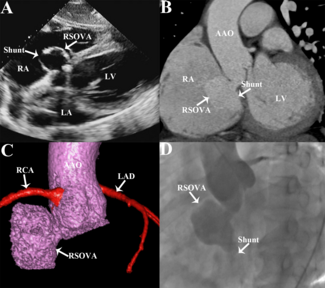

A 50-year-old man presented with chest tightness and shortness of breath after activity for 1 month. Cardiac auscultation revealed a continuous murmur in the fourth intercostal space at the right edge of the sternum.

Leizhi Ku, MD; Jianjian Wang, MD; Xiaojing Ma, PhD

An 80-year-old woman presented with intermittent dizziness and discomfort for 1 month. Electrocardiogram revealed atrial flutter, with bidirectional or inverted T-wave in leads II, III, aVF, and V2-V6.